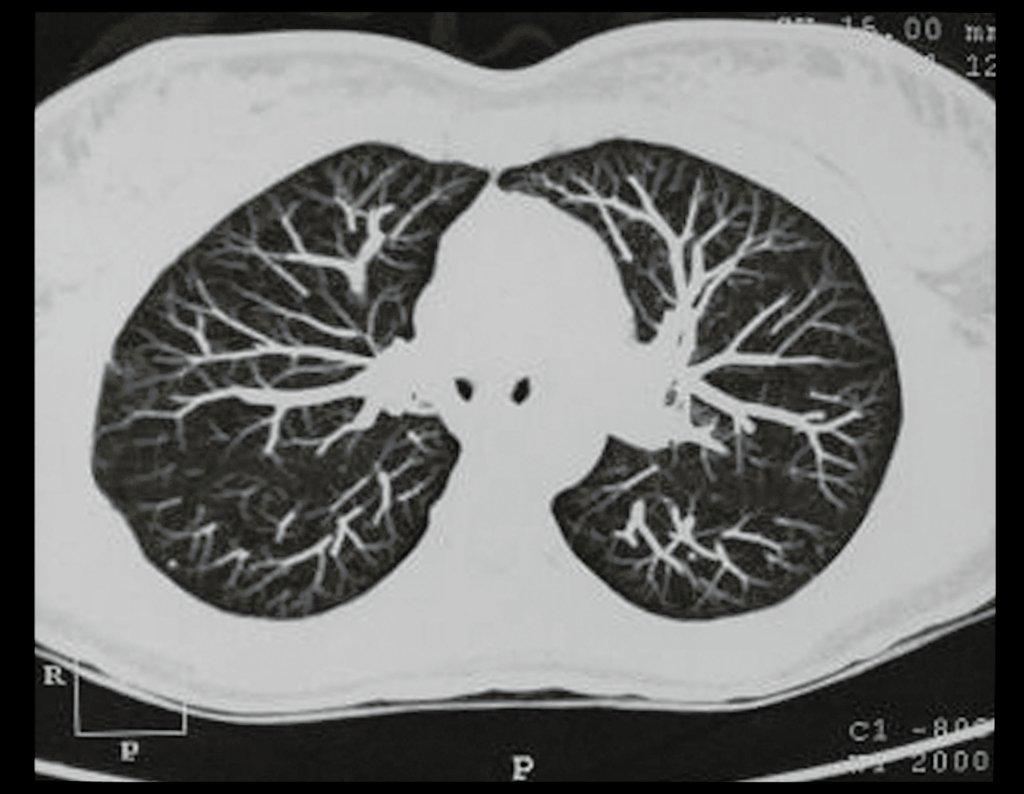

Tomografia Computadorizada (TC)

- Axial e coronal com densidade para osso e tecidos moles: Revelaram grande tumor acometendo o ilíaco esquerdo.